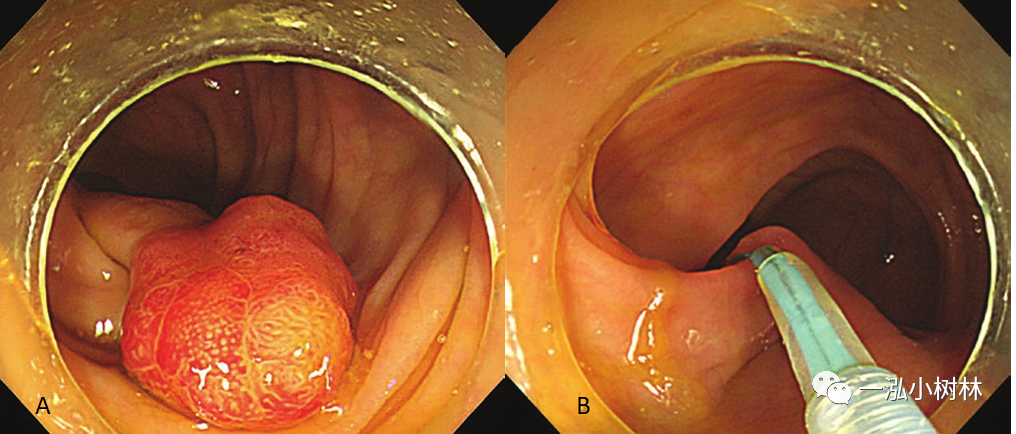

早期结直肠癌的内镜治疗_医学界-助力医生临床决策和职业成长

直肠癌